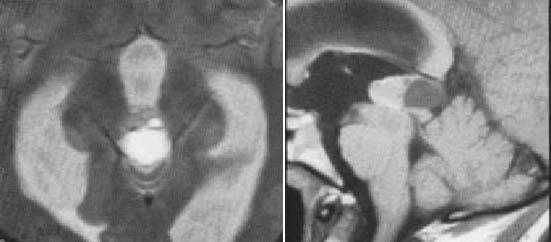

Пинеоцитома. На Т2 ВИ опухоль состоит из двух участков разной интенсивности МР-сигнала: высокой в передних отделах и низкой в задних. Четкость и линейность перехода свидетельствует о кистозном характере строения опухоли. Различия интенсивности МР-сигнала от жидкости в передних и задних отделах опухоли обусловлены эффектом «седиментации» белковых компонентов (вероятнее компонентов крови), опускающихся вниз при положении головы пациента на затылке.

Пинеоцитома. МРТ в режиме Т2 и Т1 выявляется солидного строения опухоль задних отделов III желудочка мозга. На фоне в/в контрастирования определяется выраженный и достаточно гомогенный характер контрастирования опухоли.